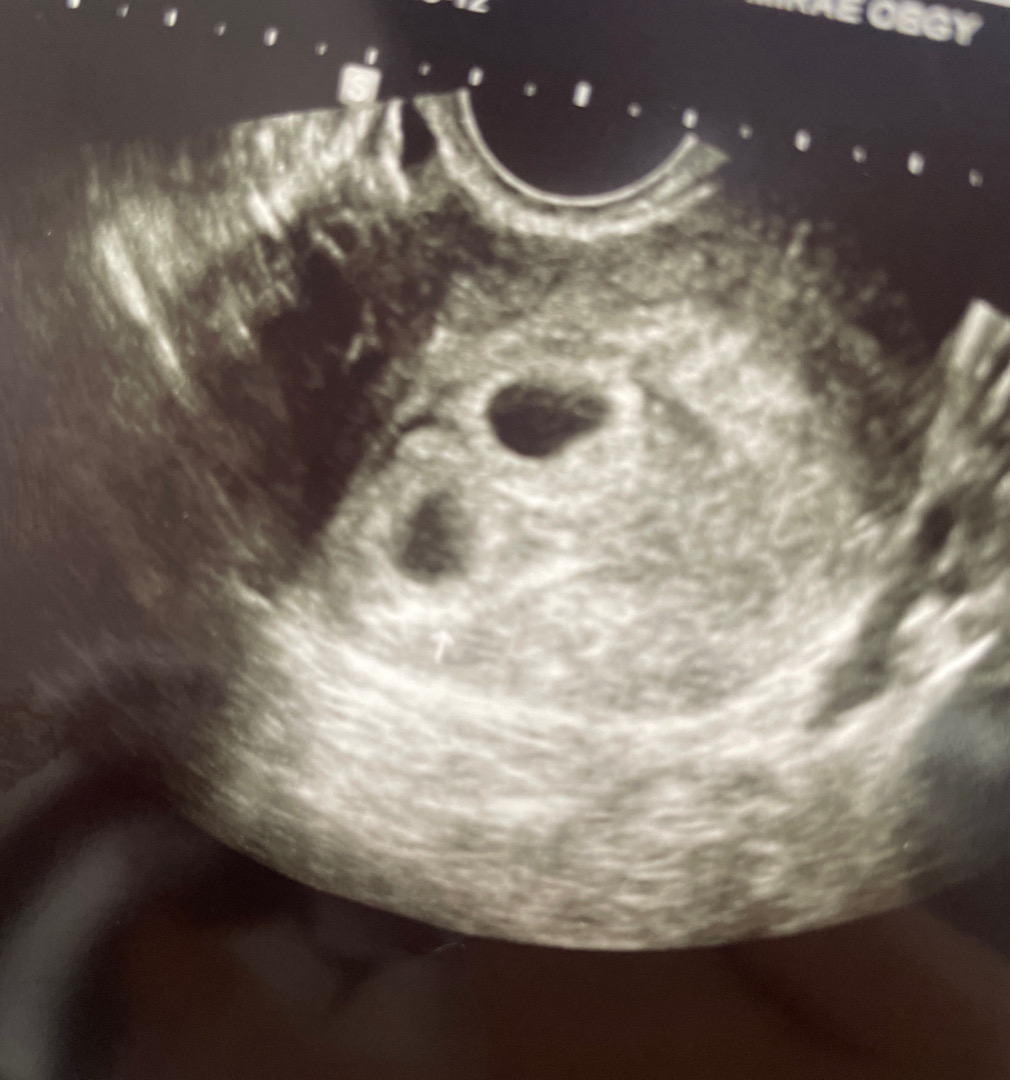

지난 토요일에 아기집 두개 애매하다고 하셔서, 3일뒤인 오늘 촘파 다시 보고왔어요! 그새 아기집이 훌쩍 커진 모습이 넘 신기하더라구요...! 💖 쌍둥이맞다면서 임신확인서도 써주시고, 바우처 신청까지 하고 보건소가서 임산부뱃지랑 이것저것 선물들 다 받아왔네용! 쌍둥이라 다 두 배씩 주셨어요 흐흐 자연임신이라 둥이들이 찾아온게 당황스럽기도 하지만… 그래도 건강하게 지켜줘야겠어요!✨